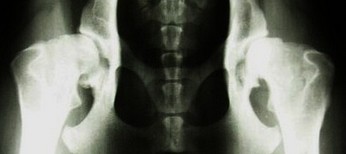

A - stawy biodrowe normalne.

B - stawy biodrowe prawie normalne i bardzo nieznaczne odchylenie od normy, ale pozwalające na rozpoznanie schorzenia.

C - dysplazja nieznaczna i niebudzące wątpliwości, wyraźne odchylenie od normy.

D - dysplazja częściowa tzw. ograniczona gdzie wyraźnie rozpoznaje się nadwichniecie będące wynikiem dysplazji.

E - dysplazja ciężka gdzie płaska, pozbawiona jej eliptycznego lub kulistego kształtu panewka występuje z przemieszczeniem głowy kości udowej.

Psy z dysplazją nie powinny być używane w hodowli z racji na jej dziedziczne przekazywanie.